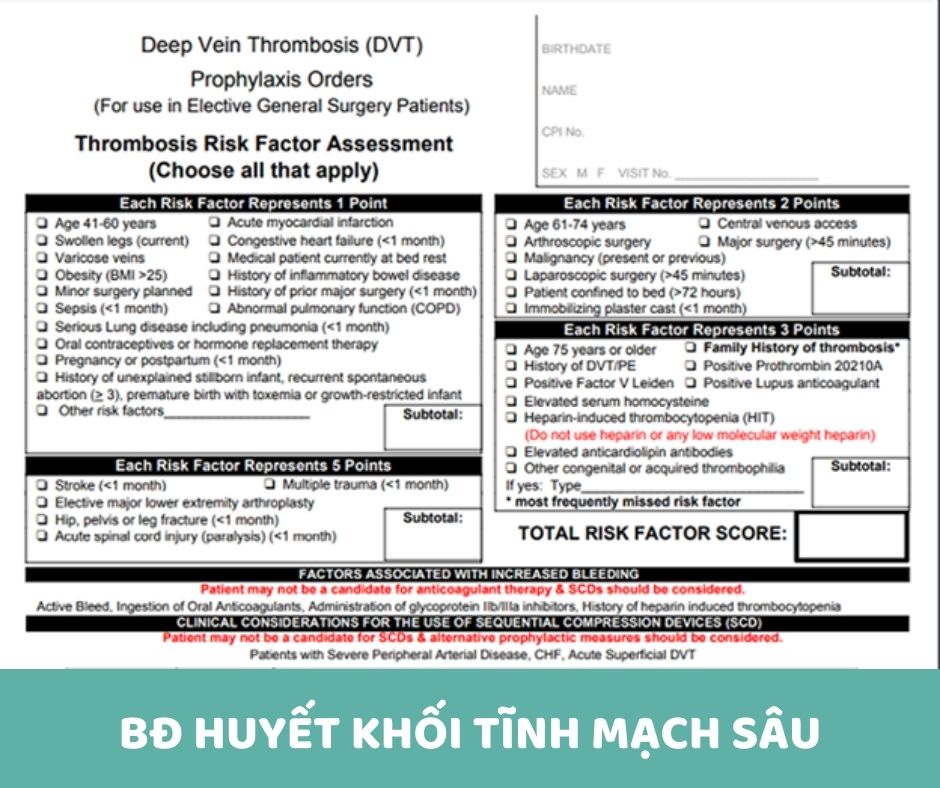

Mô hình Caprini được sử dụng trước khi phẫu thuật giúp xác định nguy cơ phát triển huyết khối tĩnh mạch sâu (DVT) của bệnh nhân

Năm 2005, Tiến sĩ Joseph Caprini đã tạo ra “ Mô hình Caprini ” để giúp các bác sĩ xác định xem bệnh nhân có nguy cơ phát triển huyết khối tĩnh mạch sâu (DVT) hay không. Ngày nay, phương pháp này được các bác sĩ chuyên khoa mạch máu sử dụng rộng rãi để giúp xác định nguy cơ phát triển huyết khối tĩnh mạch sâu (DVT) của bệnh nhân sau phẫu thuật.

Biểu đồ dưới đây cho thấy một phần đánh giá toàn diện được các chuyên gia y tế của chúng tôi sử dụng để xác định nguy cơ huyết khối tĩnh mạch sâu (DVT) sau phẫu thuật.

Nguy cơ DVT tăng lên khi có nhiều yếu tố nguy cơ hơn. Các chuyên gia về mạch máu của CVM xác định điểm 0-2, có nguy cơ thấp. Bệnh nhân có điểm nguy cơ từ 3 trở lên nên cân nhắc dùng thuốc chống đông máu (chống cục máu đông) để giảm nguy cơ phát triển DVT. Ngoài ra, liệu pháp nén có thể được khuyến khích.